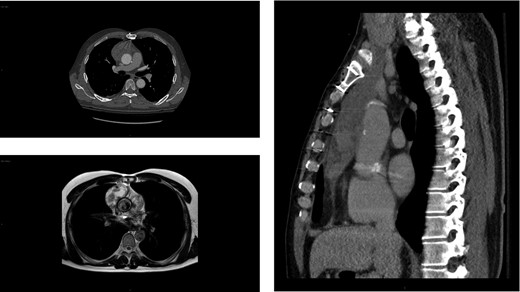

Workup at the outside hospital included computed tomography (CT) of the chest with administration of contrast material. This revealed a heterogeneous collection in the right prevascular space immediately anterior to the ascending aorta measuring 6.0 × 3.2 × 12.8 cm3, concerning for aortic rupture with contained hematoma (Fig. 1, top left and right). Vitamin K 10 mg IV was administered, and the patient was urgently transferred to our tertiary care hospital.

Imaging showing anterior mediastinal mass 4 years after a type A aortic dissection. Axial (top left) and sagittal (right) chest CT images of the large (6.0 × 3.2 × 12.8 cm3) heterogeneous collection in the right prevascular space anterior to the ascending aorta initially concerning for a rupture but contained hematoma. MRI depicting the same heterogenous soft tissue mass (bottom left). Of note, no mass was detected on the chest CT scan performed 4 years prior (not shown).

Upon arrival, the patient was hemodynamically stable with no signs of acute hemorrhage or cardiovascular compromise. The patient was admitted for monitoring and further evaluation. Contrast-enhanced CT scan of the chest was repeated at our hospital. The aortic graft appeared intact with no evidence of contrast extravasation. The configuration of the mediastinal process was stable compared to the outside study 6 h earlier. Furthermore, the appearance of the ascending graft was unchanged from a postoperative study 4 years prior. The anterior mediastinal process was consistent with a lobulated soft tissue mass such as lymphoma, thymoma or teratoma. No additional lymphadenopathy was identified. Review of remote CT imaging performed at the time of the aortic dissection did not demonstrate a mediastinal mass.

The patient underwent evaluation for an undifferentiated anterior mediastinal mass, which included CT abdomen and pelvis, testicular ultrasound and tumor markers. These were negative. Two CT-guided biopsies of the soft tissue mass were non-diagnostic. Cardiac MRI was unable to conclusively characterize the lesion (Fig. 1, bottom left). Given that this mass in the anterior mediastinum defied diagnosis by imaging and biopsy, a decision was made to operate.